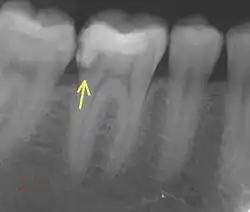

7. Radiographic examination

a. Periapical Radiographs

These provide detailed 2D images of the tooth and can detect fractures extending into dentin but may miss subtle enamel-only cracks due to their limited resolution.